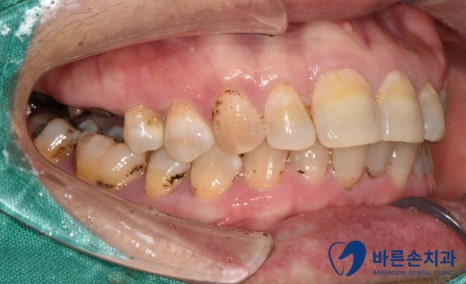

치석, 착색이 심한 초진사진.

초진 사진 입니다.

어금니가 대부분 부러져서 뿌리가 남아 있거나, 치주염으로 인해 흔들리는 상황 입니다.ㅠㅠ